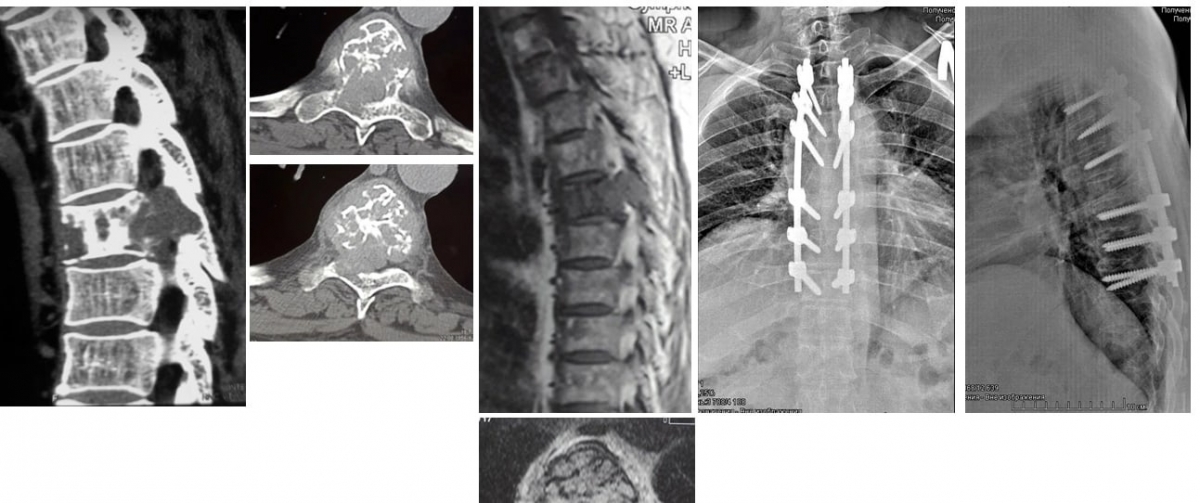

Пациент из Курганской области поступил в Центр Илизарова с нарастающей слабостью в ногах. МРТ-исследование выявило опухолевое поражение позвоночника с прорастанием ткани опухоли в позвоночный канал с компрессией спинного мозга.

«Опухоль была массивная, спинной мозг был задавлен со всех сторон. Это был метастаз рака почки. Сосуды такой опухоли в силу ряда особенностей имеют интенсивное кровоснабжение и дают сильные кровотечения при операциях. Одно из осложнений таких операций – летальный исход прямо на операционном столе от потери крови», - отметил лечащий врач-нейрохирург травматолого-ортопедического отделения №15 Сергей Алексеев .

Единственно возможным вариантом лечения данного пациента было тотальное удаление пораженного опухолью позвонка вместе с находящимся в нем, установленным в 2019 году врачами Центра, имплантатом. Причем необходимо было это выполнить крайне осторожно, чтобы не повредить спинной мозг.

Нейрохирурги Центра Илизарова произвели декомпрессию позвоночника со всех сторон и полностью удалили весь метастаз. Далее пациенту на место утраченного позвонка установили сетчатый имплантат с аутокостью - это здоровые костные фрагменты резецированных ребер того же пациента.